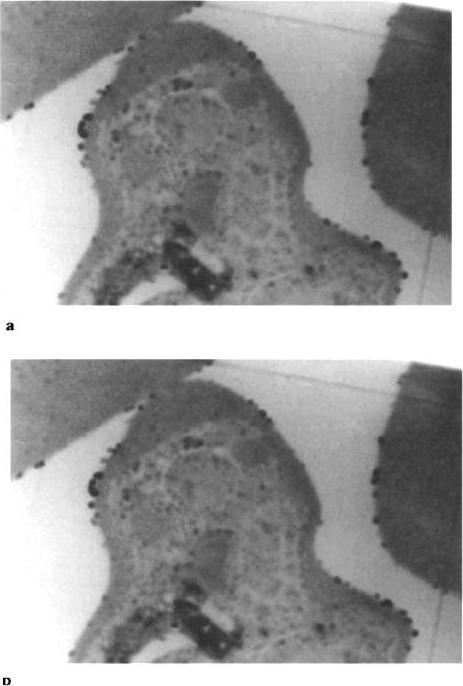

Electron micrographs of the PRBC stained with Hansson's stain for carbonic anhydrase. (a) Electron-dense reaction product of CA is seen as small dense granules along the RBC plasma membrane and throughout the cytoplasm of both unparasitized RBC and PRBC. It also is present along the parasite membrane and is present in greater abundance within the cytosol of intraerythrocytic P. falciparum (trophozoite stage) than in erythrocyte cytosole. Magnification: x 40 000. (b) Intraerythrocytic P. falciparum (schizont stage) have electrondense reaction product of CA with their cytosol and nucleoplasm, but not in food vacuole. The CA reaction product is more abundant within the parasite than in erythrocyte. Magnification: x 25 000.Sein KK, Aikawa M. The pivotal role of carbonic anhydrase in malaria infection. Med Hypotheses. 1998 50:19-23.